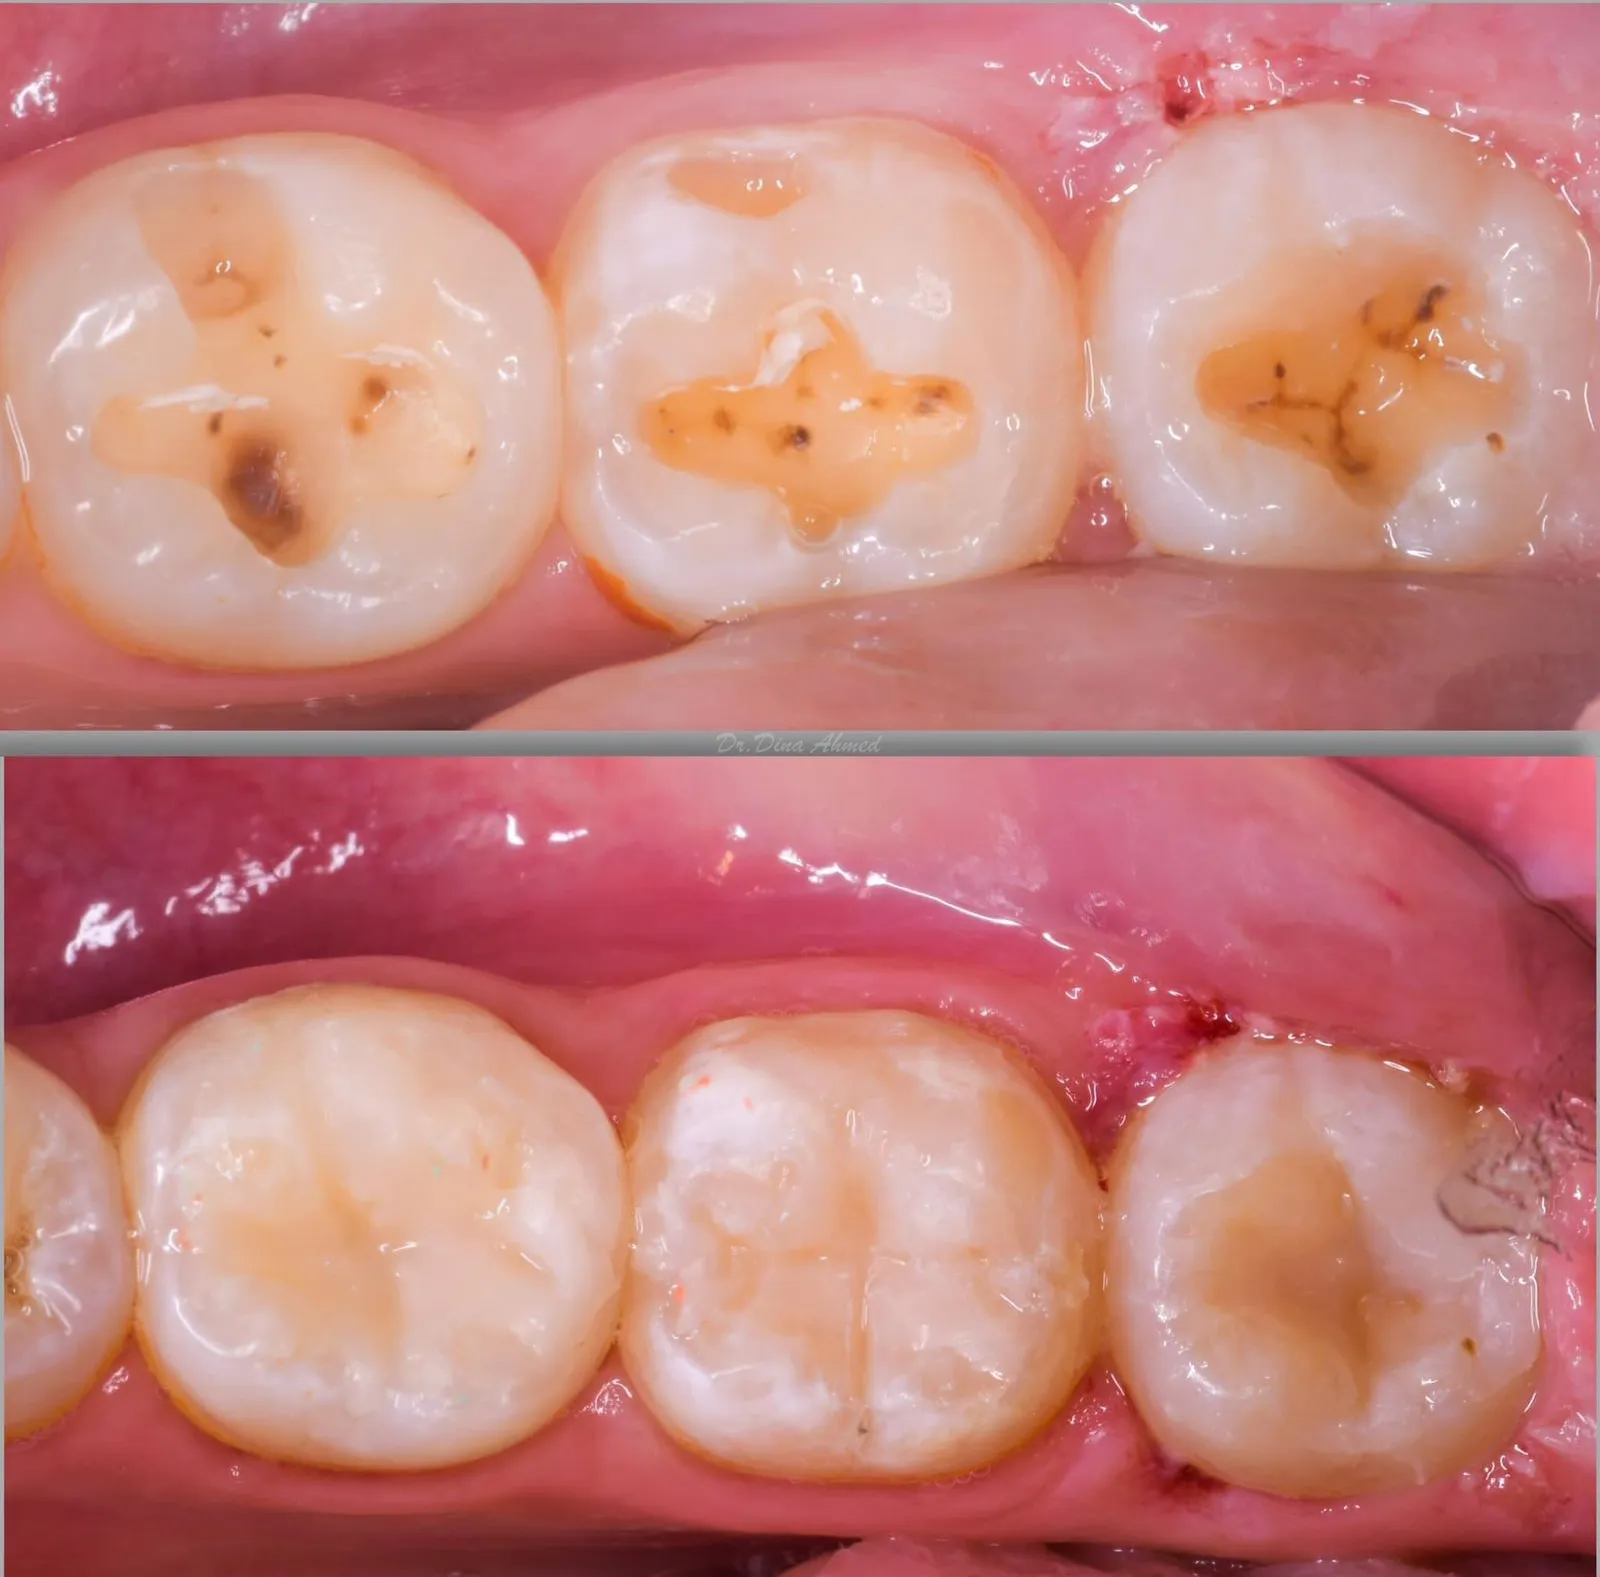

White Fillings